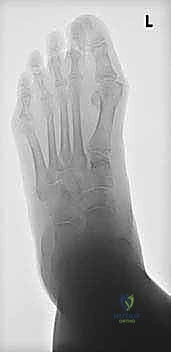

التصوير الطبي والتشخيص الإشعاعي المتقدم

لا يكتمل التشخيص الدقيق دون الاستعانة بأحدث تقنيات التصوير الطبي. يحرص الأستاذ الدكتور محمد هطيف على استخدام نهج شامل يتضمن:

- الأشعة السينية أثناء تحمل الوزن (Weight-bearing X-rays): وهي المعيار الذهبي. يتم أخذ صور من الأمام والخلف والجانبين أثناء وقوف المريض. تسمح هذه الصور بقياس الزوايا بدقة، مثل زاوية ميل الكاحل، وزاوية ميري (Meary's angle)، وتحديد موقع ذروة التشوه.